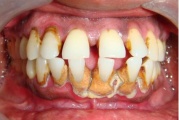

Krooniline parodontiit

Krooniline parodontiit on mikroobide poolt põhjustatud hammaste tugikudede põletik, mille tulemusena tekib progresseeruv alveolaarluu (nähtav röntgenograamil) ja periodontaalligamendi destruktsioon, igemetaskute moodustumine, igeme retsessioon või mõlemad kahjustused kombineeritult. Loe edasi »

- igemed veritsevad (19)

- igemed punetavad (21)

- ige on paistes (mädapunn)

- igemed on tursunud/vohavad (17)

- igemepiir on taandunud (3)

- hammaste asukoha muutus (5)

- puudulik suuhügieen (5)

- igemepealne hambakivi (5)

- igemealune hambakivi (4)

- vahed hammaste vahel (5)

- halb hingeõhk / suu haiseb (12)